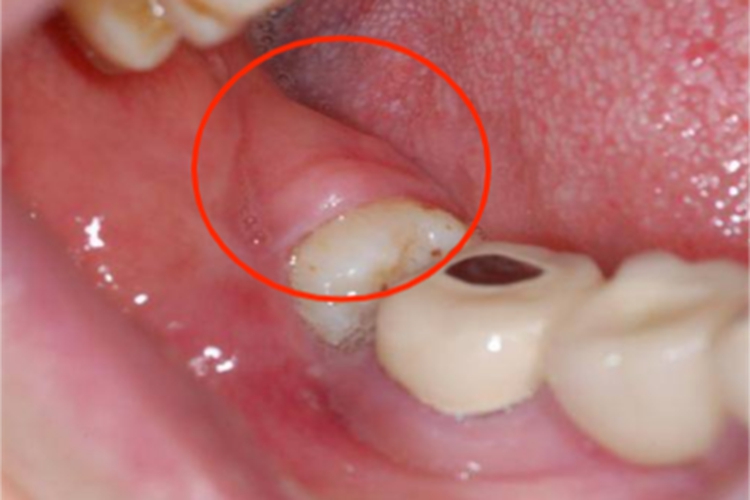

智齿冠周炎患者可出现磨牙后区疼痛,甚至牙龈肿胀为大包样,边界不清,压痛明显,患者可出现吞咽疼痛,伴有不同程度的张口受限等症状。

智齿冠周炎主要与口腔卫生差等因素有关。临床上智齿在萌出过程中形成与口腔相通的盲袋,盲袋内易存储食物残渣、唾液、细菌,在适宜的口腔温度和湿度环境中很容易滋生细菌,容易引发智齿冠周炎。